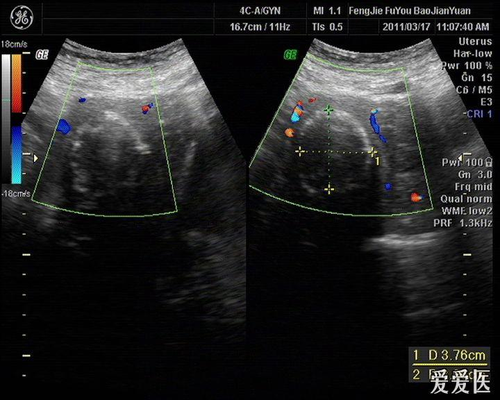

子宫内膜钙化通常发生在子宫肌瘤透明变性和坏死以后。因为子宫肌瘤的血液循环受到阻碍,子宫内的钙盐被其组织成分和其它变性的物质吸收并且沉积,形成了营养不良性的钙化”,也就是子宫内膜钙化斑。

形成子宫内膜钙化斑也与一些人为原因有关,例如许多女性朋友进行人流或是药流,却没有流不干净,亦或者女性生产以后的残留物,在坏死后遗留形成钙点、钙斑。当然,有些女性患者有结核病史,子宫内膜也可能形成钙化。子宫内膜钙化需要经过宫腔镜或是诊刮后的相关病理检查才能够最后确诊。需要注意的是,如若患有结核性的子宫内膜炎极可能影响生育,所以发现身体有异样,一定要去往医院检查,及早发现及早治疗。